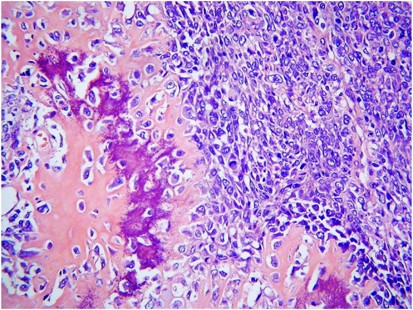

A histological diagnosis of carcinosarcoma depends on identifying high-grade malignant epithelial and mesenchymal components typically showing a sharp demarcation between both, although occasionally this demarcation may be blurred (Figure 1). The epithelial element may include serous, grade 3 endometrioid, clear cell and undifferentiated carcinoma in order of frequency. Admixtures may be seen and typing of the epithelial component may be difficult; in some cases, a hybrid morphology (with features of serous and endometrioid carcinoma) or a malignant squamous component is present (Figure 2), which may be a clue to the diagnosis. The mesenchymal component can be homologous or heterologous. The former is typically a high-grade sarcoma, NOS and eosinophilic hyaline globules are frequently noted. If heterologous elements are present, then rhabdomyoblasts or malignant cartilage is the most common. Osteosarcomatous and liposarcomatous differentiation may rarely occur (Figure 3). On occasion, carcinosarcomas are associated with a component of primitive neuroectodermal tumour (PNET); in such cases, markers such as neurofilament, glial fibrillary acidic protein (GFAP) and synaptophysin may be useful in highlighting this component, which is more analogous to a central than a peripheral PNET without EWSR1 gene rearrangement.9 Occasional examples of a yolk sac tumour component and melanocytic differentiation have also been reported.10, 11